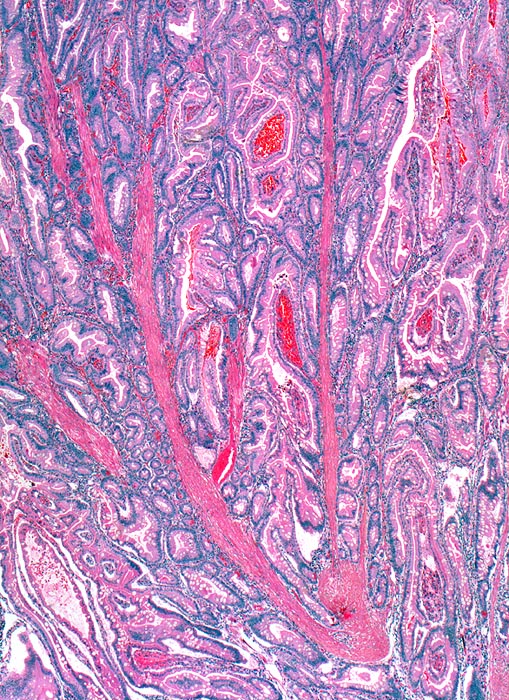

PathoPic – image database / PathoPic ID 3057 - Peutz Jegher Polyp

Peutz Jegher Polyp

Jejunum

Der hamartomatöse Polyp besteht aus arborisierenden Strängen glatter Muskulatur bedeckt von Lamina propria und einem enterischen Epithel bestehend aus absorptiven Zellen, Becherzellen und Paneth Zellen.

Breitbasiger Polyp von 3cm Durchmesser.

Epithelverlagerungen in die Submukosa und Muscularis propria kommen nur in Dünndarmpolypen vor.

Histologie

25